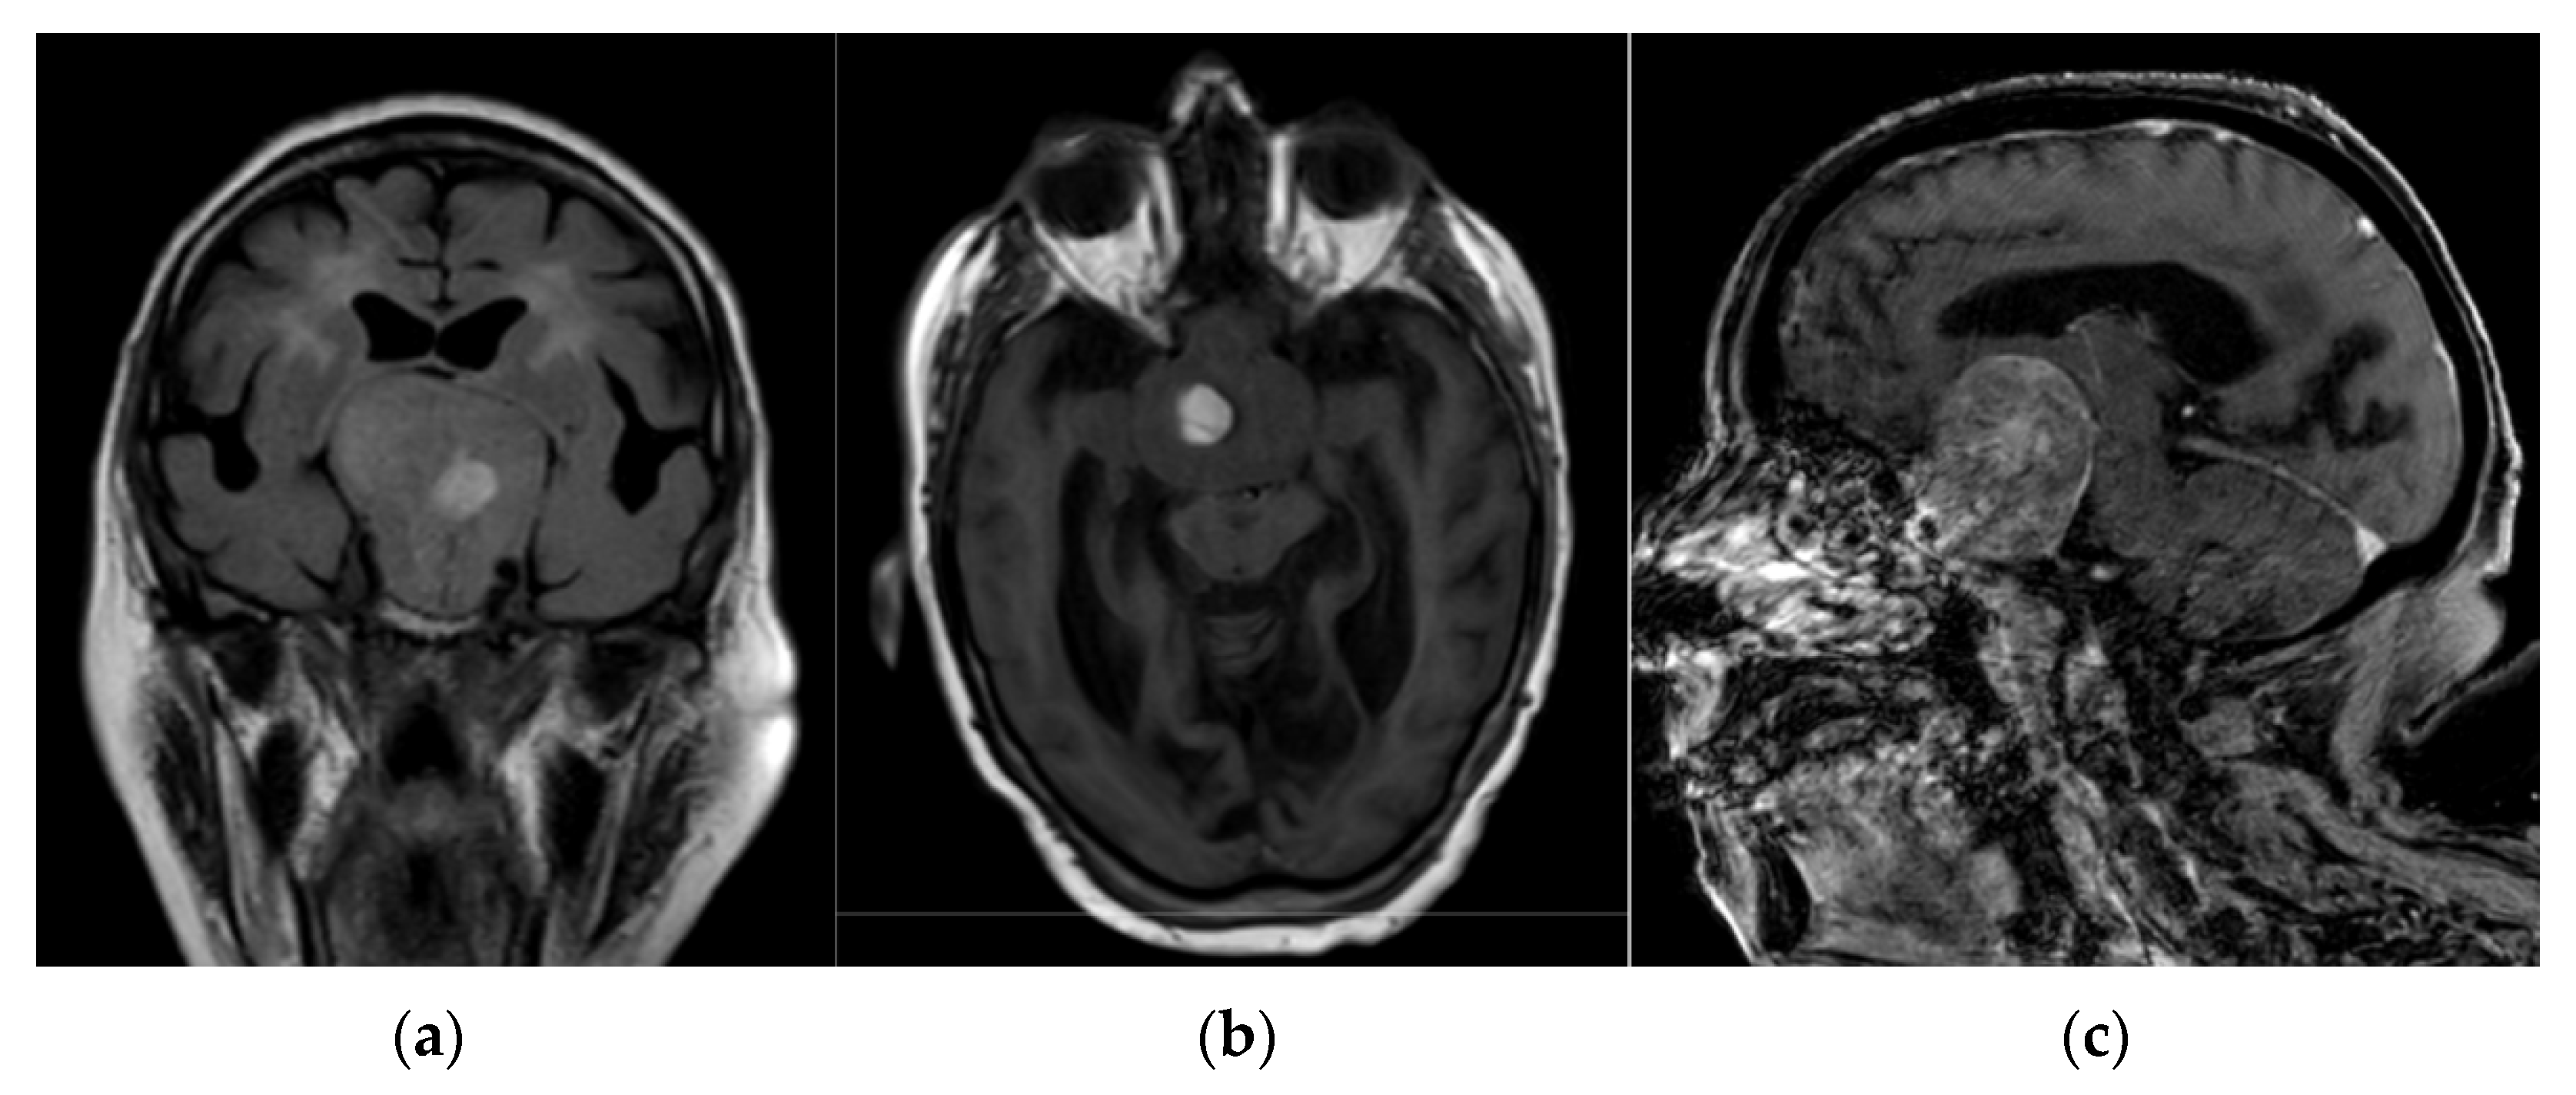

2. Case Presentation